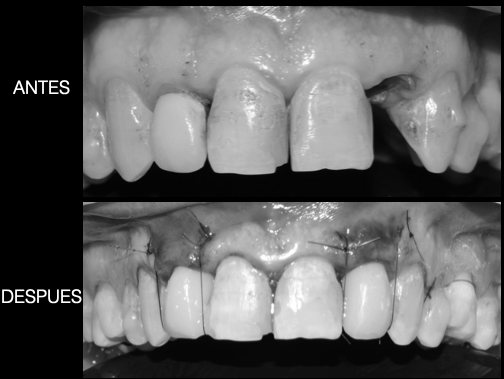

Os enseñamos este nuevo caso el Dr. Arturo Sánchez Colodro en nuestra clínica dental de Jaén, nos muestra un caso de cirugia plástica periodontal con injerto de tejido conectivo subepitelial en recesiones inferiores en paciente con sensibilidad y recesión de las encías de los dientes inferiores por trauma oclusal y cepillado inadecuado. Este caso ha sido tratado con la última y más avanzada tecnología en digitalización dental. Mostramos el resultado después de la operación realizada, el resultado en la revisión un año después y la comparativa del antes y después.

Resultado final (antes-después):